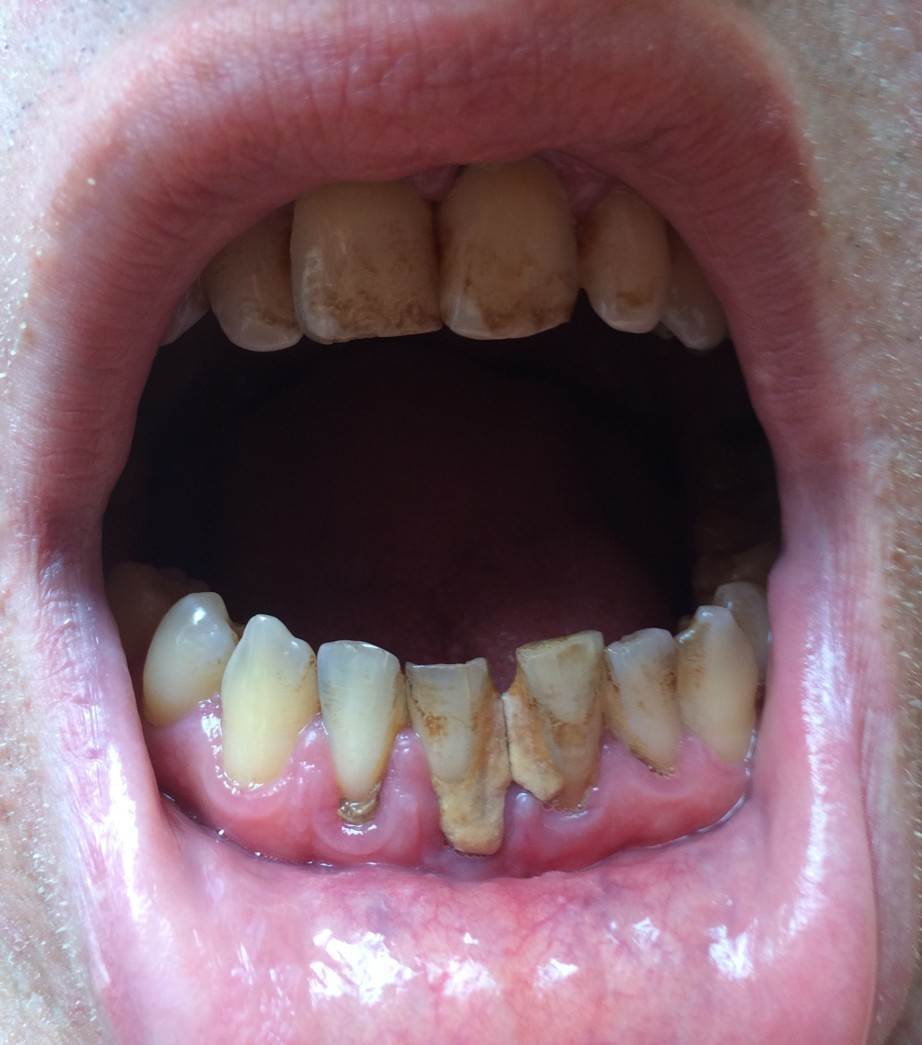

Sergey-010101 Опубликовано 5 октября, 2025 Поделиться Опубликовано 5 октября, 2025 (изменено) Здравствуйте. У меня на нескольких передних зубах большие камни, рецессия десны, на миллиметров 5-6 камень опускается спереди и сзади зуба. В одной стоматологии предложили чистку ручными инструментами. В другой аппаратом Вектор. Что являет более безопасным для чистки камней на корнях? Какой вариант выбрать? Вектор вроде ультразвук использует. А пишут что ультразвуком камни на корнях вредно чистить. Есть ли у Вектора какие то варианты? Насадки? Если выбрать этот способ есть моменты которые нужно уточнить? Обратить более подробное внимание. Изменено 5 октября, 2025 пользователем Sergey-010101 Ссылка на комментарий

Sergey-010101 Опубликовано 5 октября, 2025 Автор Поделиться Опубликовано 5 октября, 2025 И что делать если будут шататься потом, чтобы сохранить? Как нарастить десну кость? Немного есть мнения что есть риск потери. Но в целом несколько врачей сказали что могут даже не шататься. Убыль кости есть на 2-3 мм в некоторых местах, но корень более чем на половину в кости. Ссылка на комментарий